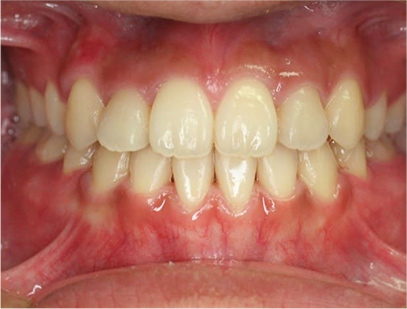

治療後

• 正面

治療前の写真を比べると上下の前歯は綺麗に並び、歯が出ていたことも改善され、 上下の歯はしっかり咬み合っています。 治療期間は、重度の開咬であったために3年弱を必要としました。

• 歯並びが綺麗になり、上下の歯が咬み合った事。

• 上の前歯が出ていたことが改善された事。